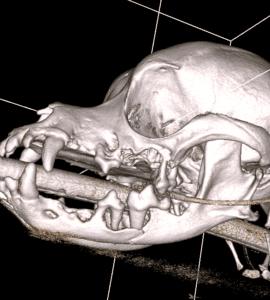

CBCT is especially helpful in trauma cases. While dental radiographs can only show fractures that occur where there are teeth, CBCT can show us fractures in any part of the skull. Having all of the information allows us to make better decisions for pets in regard to treatment and the potential long-term effects of an injury. Here is an image of a left lower jaw fracture: